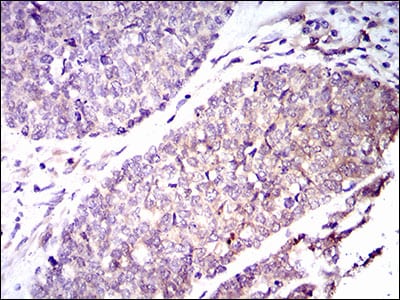

Immunohistochemical analysis of paraffin-embedded human esophageal cancer tissues using GUCY1A3 mouse mAb with DAB staining.